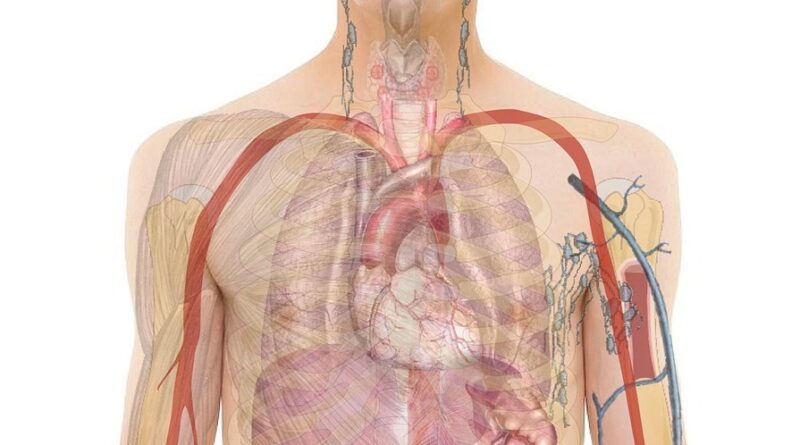

Rano otkrivanje raka može doslovno spasiti život. Mnogi rani simptomi često prođu neprimijećeno ili se pripišu stresu, umoru ili starenju. Važno je pažljivo pratiti signale koje tijelo šalje kako bi se bolest prepoznala u početnim fazama, kada je liječenje najefikasnije.

U nastavku donosimo 20 najčešćih ranih znakova raka na koje treba obratiti pažnju. Prepoznavanje ovih simptoma i pravovremeni ljekarski pregled mogu značajno poboljšati ishod liječenja.

1. Otežano disanje ili kratki dah

Ovaj simptom može biti jedan od prvih znakova raka pluća. Ako primijetite da vam je disanje otežano čak i pri manjem naporu, potrebno je konzultirati ljekara.

2. Hronični kašalj ili bol u grudima

Uporan kašalj bez prehlade, praćen bolom koji se širi u rame ili ruku, zahtijeva dodatnu provjeru, posebno kod pušača ili osoba izloženih zagađenju zraka.

3. Česte infekcije ili povišena temperatura

Ponavljajuće infekcije i groznice mogu ukazivati na poremećaje u krvnim ćelijama, uključujući leukemiju, te ne treba ih ignorisati.

4. Poteškoće s gutanjem

Ako osjećate bol ili nelagodu pri gutanju, to može biti rani simptom raka jednjaka ili grla. Pravovremeni pregled može otkriti promjene prije nego što postanu ozbiljne.

5. Natečeni limfni čvorovi

Otečeni limfni čvorovi, naročito ako traju duže od dvije sedmice, mogu ukazivati na poremećaje u imunološkom sistemu ili rane faze raka.

17. Oticanje lica ili crvenilo

Može biti povezano s tumorima u grudima koji pritiskaju krvne sudove i uzrokuju vidljive promjene u licu.